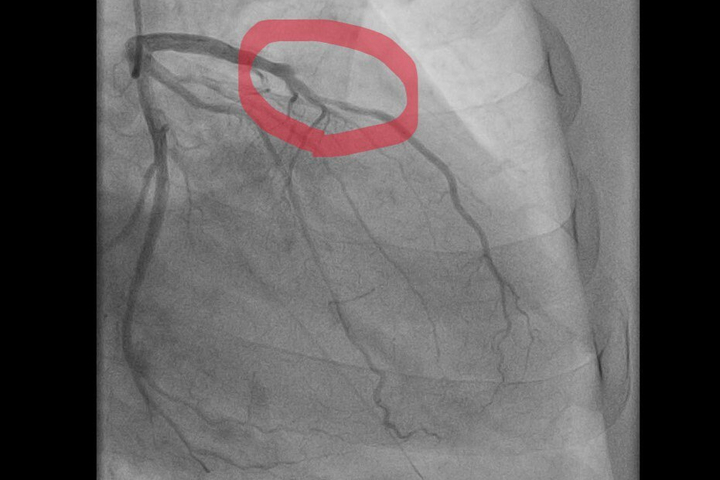

«Пациент, мужчина 59 лет, поступил после того, как почувствовал острую боль в груди во время уборки снега. Бригада „скорой“ диагностировала острый инфаркт миокарда. В ходе обследования была выявлена острая тромботическая окклюзия передней межжелудочковой артерии — сосуда, который неофициально называют „артерией вдов“ из-за высокой летальности при его поражении», — рассказали в балаковской больнице.

Операционная бригада выполнила экстренное стентирование артерии, в результате чего её проходимость была полностью восстановлена. После этого пациента выписали для продолжения реабилитации на амбулаторном этапе.